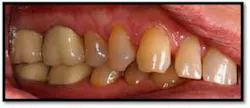

Ill-fitting posterior crowns are a plaque and food trap which are contributing factors in posterior inflammation and pocketing

UR/LR Pre TxThe tissues around the posterior crowns are almost bluish in color(above left)UL/LL Pre Tx:

Pockets 4-6mm, gen posterior BOP

UL/LL Pre TxUL/LL Pre Tx reflected in a mirror